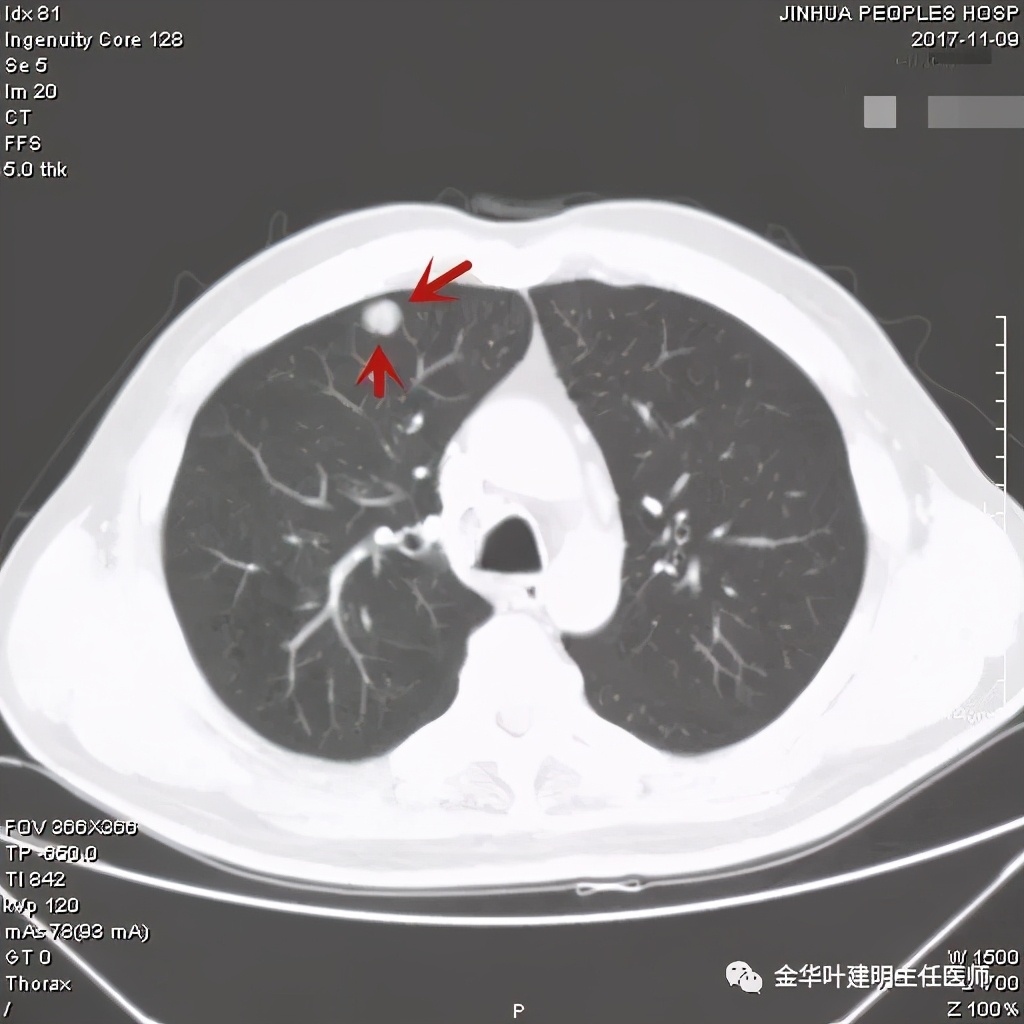

金华的某A,男性,70岁,因检查发现右上肺占位入院,没有临床症状,肿瘤筛查指标正常,血常规与CRP正常。胸部CT检查报告考虑恶性可能:

直径约2.4厘米,密度欠均,血管贴边,增强轻度强化。单从描述看,恶性可能性较大。我们再来看看图像:

可见右上叶占位,我们现在知道了结果以后回头看,发现病灶的边缘在各个层面都是过于光滑(绿色箭头所示)。血管紧贴病灶边走行(桔色箭头所指),是不是有侵犯看不清楚,若是靶扫描加重建可能会更清楚点。支气管感觉也是贴着病灶走,但有的层面是不是截断,也不看的不太清楚。有的层面见局部有点状高密度(蓝色箭头所指),是不是错构瘤的局部钙化呢?若是纵隔窗又是如何?

事前来看,达2.4厘米的不均质实性肿块,增强有轻度不均匀强化,血管贴边走行,支气管疑有截断,恶性不能除外,而且可能性较大。但现在经过手术已已经证实是错构瘤的情况下,我们回头来看,其实有许多不符合恶性的地方:

1、病灶的每个层面,边缘都过于光滑了。肺癌一般到这个大小总要有棘突、分叶、毛刺、牵拉周围胸膜等边缘异常的征象;

2、肿瘤大于2厘米以上,又紧贴血管,多有血管走行异常、受侵或血管进入等征象;

3、支气管截断不确切,若术前能三维重建或支气管镜检查可能能明确是否有支气管受累;而且占位致支气管截断,容易有刺激性咳嗽症状;

4、轻度强化是否可靠?肿瘤达2.4厘米,是否强化会比较明显,因为血供要求较多呀。

肿瘤不能除外,手术是正确及时的,回头看不知道有没有局部楔形切除或剜出肿瘤的可能性?下面是标本的病理:

其实我们发现,包括今天这例,只要是错构瘤,“边缘非常光滑”是每一像都具备的!虽然有的似有支气管截断、有的似有血管征、有的似有分叶,但总的只要是边缘非常光滑的实性占位,就要想到错构瘤的可能,若有点状钙化密度,更是强烈要考虑。错构瘤如何靠近胸膜,其实可以切开一点肺实质,挤一下,肿瘤就会滚出来。